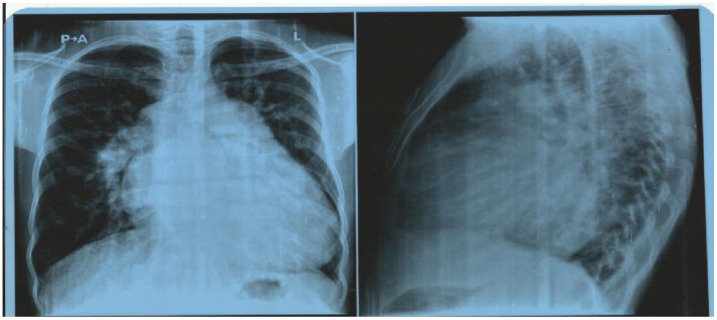

大多数室间隔缺损患者都能活到成年,这就为肺动脉高压等其他并发症的逐渐发展留出了时间。如果伴有其他心脏疾病(如瓣膜性心脏病),也会导致肺动脉高压的发生,那么肺动脉高压可能会加重。由于肺动脉高压的这些不同病因具有不同的机制,它们的并存会使患者的治疗变得复杂。我们介绍了一名患有室间隔缺损和风湿性二尖瓣疾病的 26 岁男性患者,他患上了严重的肺动脉高压,并与心房颤动和后来的心脏性猝死并发。

Most individuals with ventricular septal defect survive to adulthood which allows time for other complications such as pulmonary arterial hypertension to gradually develop over a period of time. When there are other associated cardiac conditions that also contribute to the development of pulmonary hypertension such as valvular heart disease, the pulmonary hypertension may be exaggerated. Because these different etiologies of the pulmonary hypertension have different mechanisms, their coexistence can complicate patient management. We present a 26-year-old man with a large ventricular septal defect and rheumatic mitral valve disease who developed severe pulmonary hypertension that became complicated by atrial fibrillation and later sudden cardiac death.